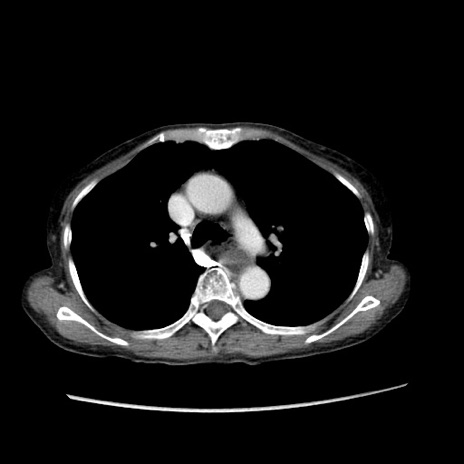

症例25(横断像)

【症例】80歳代女性

【主訴】胸のつかえ感

【現病歴】約9時間前に食後から胸のつかえた感じあり、嘔吐あり、来院。

【既往歴】胃癌(全摘)、胆摘、虫垂炎

【身体所見】心窩部に圧痛あり、反跳痛なし。

【データ】WBC 5700、CRP 0.05